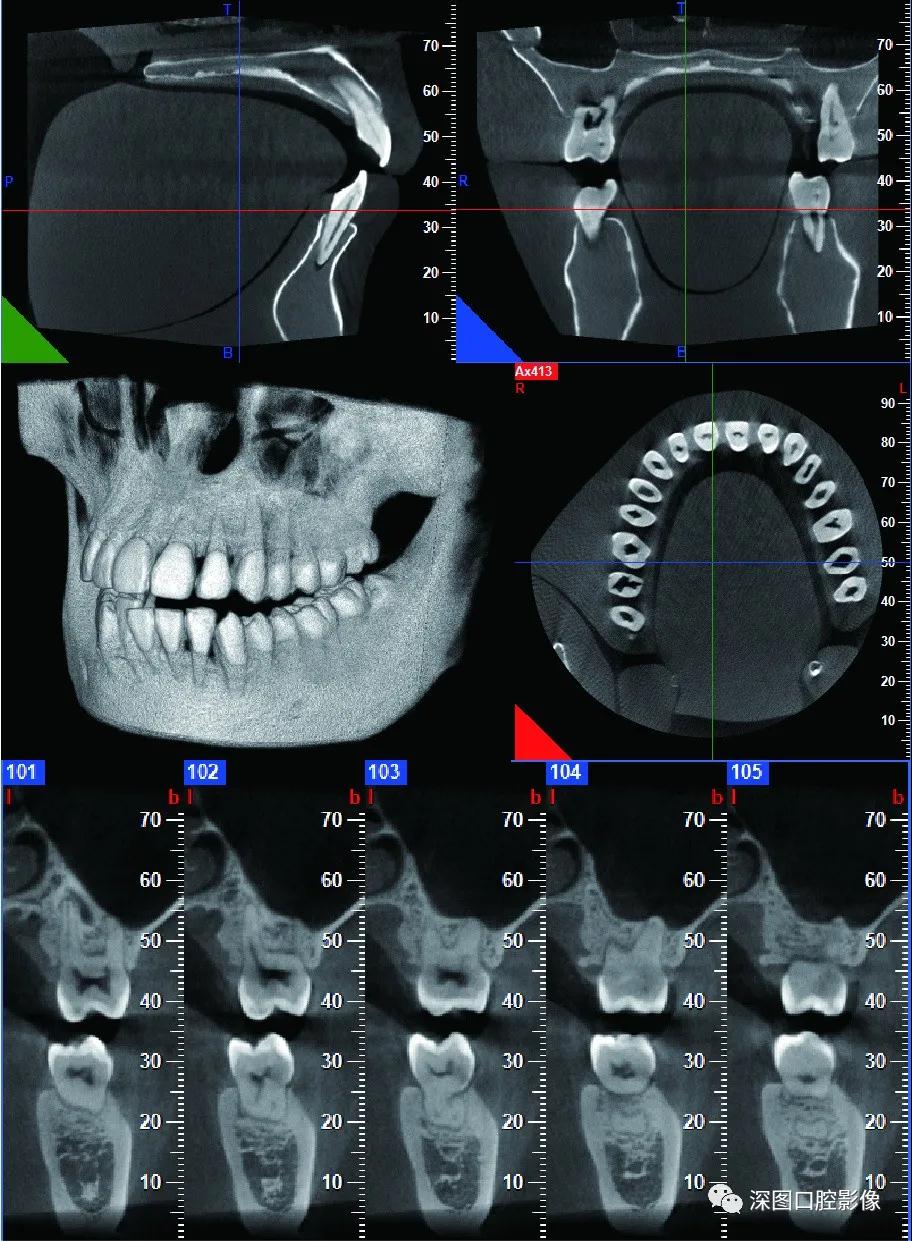

01深图口腔锥形束CT